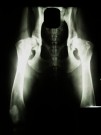

Příklady vyhodnocení DKK

kloubní štěrbiny symetrické, úzké, hlavice hluboko uvnitř jamek, středy hlavic více než 2 mm za okrajem jamky, hlavice kulovité, krček dobře ohraničený, přední okraje kyčelních jamek úzké, ostře ohraničené, Norbergův úhel 110 stupňů, žádné znaky artrózy.

kloubní štěrbiny mírně nesymetrické, úzké, středy hlavic těsně uvnitř za okrajem jamky, hlavice kulovité, přední okraj jamek mírně zesílený, bez znaků artrózy, Norbergův úhel 107 stupňů.

kloubní štěrbiny nesymetrické, rozšířené, středy hlavic těsně vně okrajů jamky, hlavice mírně oploštělé, patrné zesílení v úponu kloubního pouzdra, tzv. Meduza linie, přední okraje jamek zesílené, počínající artróza, Norbergův úhel 102 stupňů.

obě kloubní štěrbiny silně nesymetrické, rozšířené, středy hlavic vně okrajů jamky, hlavice oploštělé, krčky zkrácené, přední okraje jamek velice zesílené, opotřebené, vlevo středně, vpravo mírně pokročilé artrózní změny, Norbergův úhel 92 stupňů.

kloubní štěrbiny zcela nesymetrické, středy hlavic daleko vně okraje hlavic, hlavice zcela deformované, krček neohraničitelný, silná artróza s rozsáhlou tvorbou výrůstků, Norbergův úhel pod 90 stupňů.

vlevo kloubní štěrbina zcela nesymetrická, široká, střed hlavice daleko vně za okrajem jamky, přední okraj jamky zcela opotřebený, hlavice silně deformovaná, hřibovitá, krček zkrácený, zesílený a těžko ohraničitelný, Norbergův úhel méně než 90 stupňů, pokročilá artróza, vpravo kloubní štěrbina ve vnější třetině divergentní, střed hlavice 1 mm uvnitř za okrajem jamky, hlavice kulovitá, přední okraj jamky ve vnější části mírně šikmý, zesílený, Norbergův úhel 105 stupňů.

vlevo kloubní štěrbina zcela nesymetrická, široká, střed hlavice daleko vně za okrajem jamky, přední okraj jamky zcela opotřebený, hlavice silně deformovaná, hřibovitá, krček zkrácený, zesílený a těžko ohraničitelný, Norbergův úhel méně než 90 stupňů, pokročilá artróza, vpravo kloubní štěrbina mírně nesymetrická, rozšířená, střed hlavice přímo na okraji jamky, hlavice se znatelným zesílením v oblasti úponu kloubního pouzdra - tzv. Meduza linie, přední okraj jamky zesílený, počínající artróza, Norbergův úhel 105 stupňů.